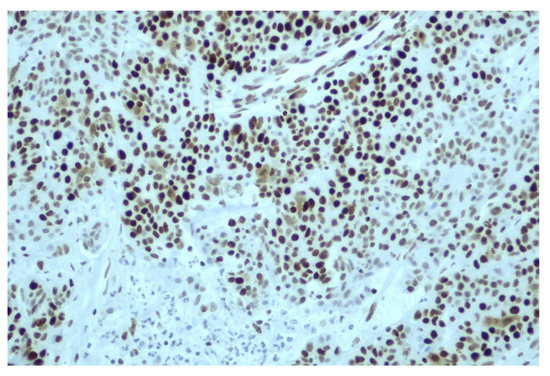

2.1. Immunohistochemistry (IHC) Testing